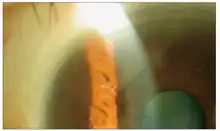

Ganciclovir was injected into the eye and the cornea returned to a normal state.